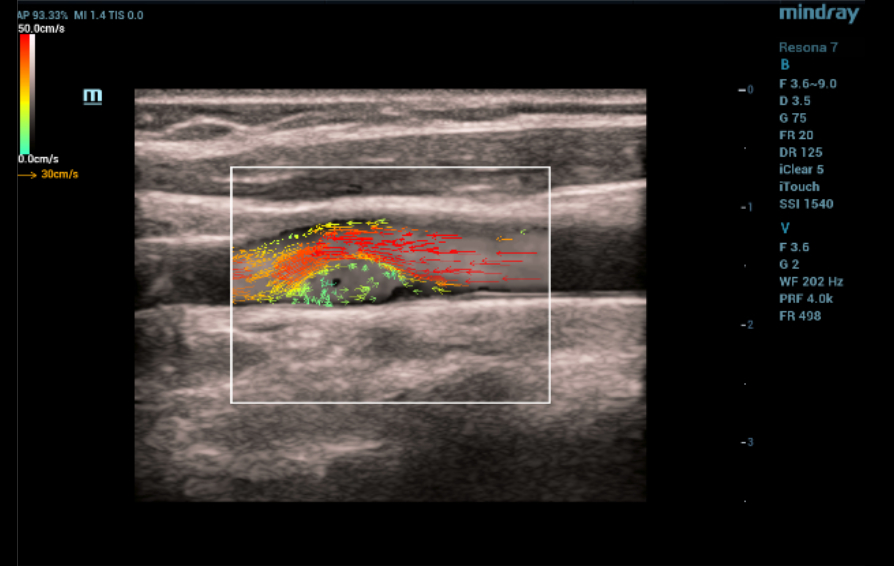

Ultrasound examination ŌĆō vector analysis of blood flow mode (V Flow)

When the vector analysis mode (V Flow) was activated, the complete filling of the lumen of the left common carotid artery in the bifurcation area with colored vector arrows was clearly traced. The following changes were registered immediately after the linear hyperechoic structure: 1) shorter color arrows compared to arrows from the main blood flow in the vessel; 2) the arrows had a different color pattern (green, blue, yellow) in contrast to the red and orange arrows of the main stream; 3) the short arrows had a multidirectional, vortex-like direction in contrast to the laminar flow, which was determined over the pathological area of the vessel with a hyperechoic linear structure (Fig. 4). Given the absence of signs of flotation of hyperechoic linear formations and the topical symmetry of the location, it was assumed that these changes are characteristic of the carotid web.

Ultrasound vector analysis of blood flow

The V Flow mode made it possible to clearly see the full filling of the vessel lumen with colored arrows directly behind the hyperechoic linear formation on the left. The direction, color and size of the arrows in this area of interest clearly provided information about the slow-speed, retrograde and then vortex-like flow of blood in the vessel, which explained the poor color filling of the vessel lumen directly behind the hyperechoic linear structure in the color Doppler mapping mode, due to the high dependence of the latter on the speed and direction of moving blood particles (erythrocytes). The technology of vector analysis of blood flow made it possible to exclude the presence of an atherosclerotic plaque or a parietal thrombus.